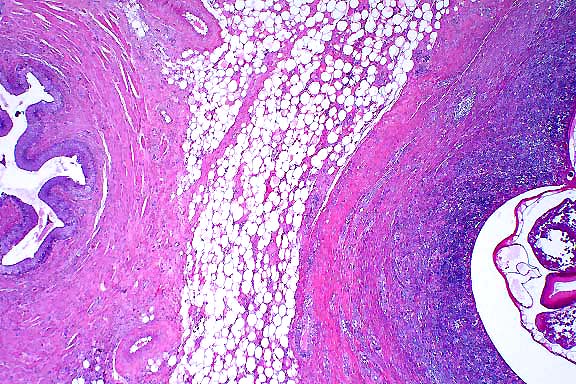

4x

obj.

- Case 23-1. Heart. The epicardium is markedly thickened

by fibrosis and a superficial exudate composed of caseous necrotic

debris, a dense cellular infiltrate, with multinucleate giant

cells and scattered 50u diameter yeast spherules.

20x

- Case 23-1. Epicardial exudate. Immature spherules

have a hyaline eosinophilic capsule and contain granular basophilic

material. Mature spherules contain abundant 2u diameter endospores.

Spherules are surrounded by numerous neutrophils, fewer macrophages,

multinucleate foreign body giant cells, lymphocytes and plasma

cells.